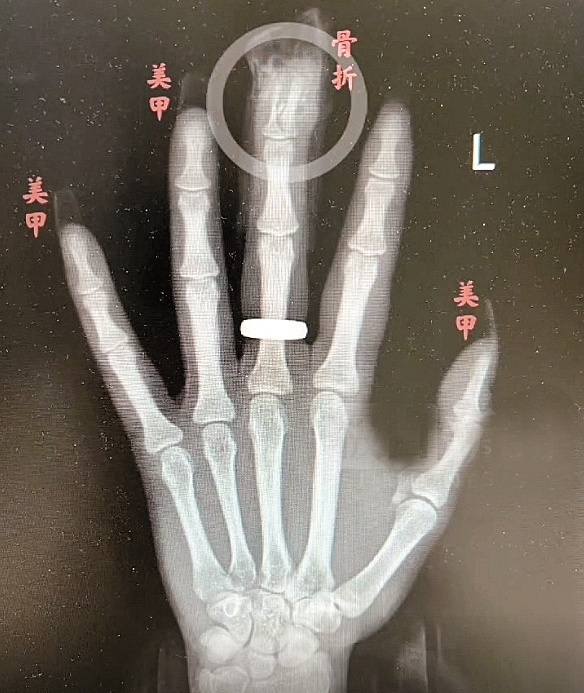

“两根手指末端指骨粉碎性骨折 , 甲床破裂 。 ”接诊的手外科主任冯伟医生告诉极目新闻记者 。 相关检查显示 , 江女士左手中指、环指末端指骨均粉碎性骨折 , 甲床破裂 , 其余多根手指软组织挫裂伤 。 手术中 , 医生用一根克氏针复位固定了江女士骨折的手指 , 并用极细的手术缝合线缝合甲床 。 幸运的是 , 江女士指尖末端血供不错 , 术后恢复较好 。 但由于骨折严重 , 术后还需要康复锻炼才能争取恢复指尖的屈曲功能 , 由于甲床受损 , 半年后重新长出来的指甲可能会没有以前那样平整美观 。

对于江女士的伤情 , 冯伟分析 , 江女士甲片长度是正常指甲长度的2倍 , 又有一定向下的弧度 , 摔倒的瞬间 , 受到极大冲击力 , 同时 , 手指触地时指甲比手掌更早接触地面 , 再加上甲片被胶水牢牢固定 , 这时 , “甲片就像个杠杆 , 直接掀翻指甲 , 导致指骨骨折 。 ”冯伟说 , 如果没有美甲 , 伤害远没有现在严重 。